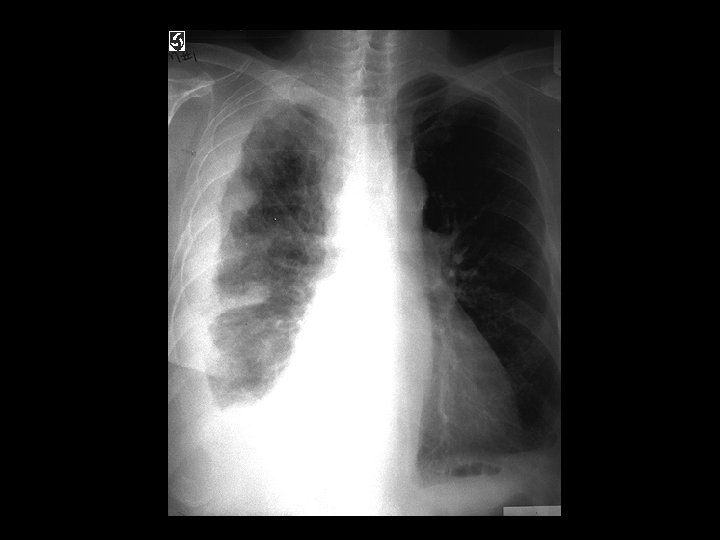

Tuberculosis • Findings: – patchy parenchymal opacities – focal bronchiectasis and accompanying bronchioliltis – bilateral distribution • ddx: – endobronchial spread of tumor